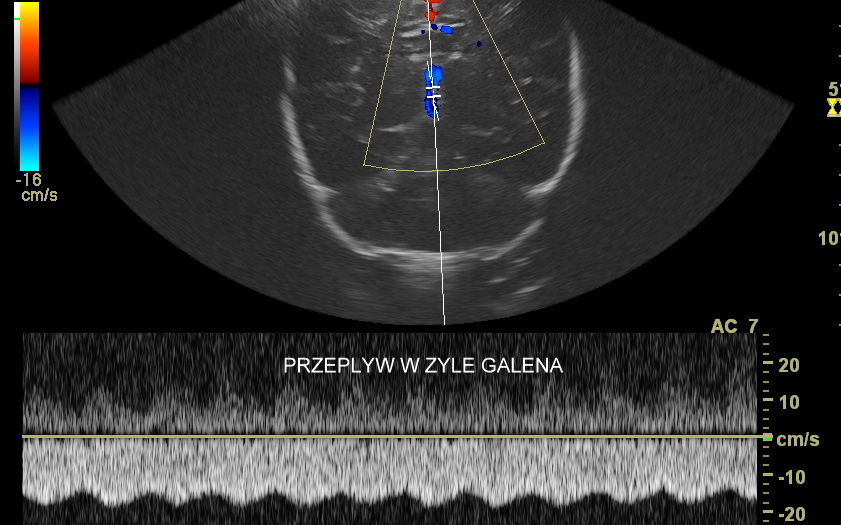

USG główki to podstawowa metoda diagnostyczna mózgu i struktur okołomózgowych u wcześniaków, noworodków i niemowląt. Badanie jest bezbolesne i nieryzykowne w porównaniu do rezonansu magnetycznego, podczas którego dziecko poddawane jest znieczuleniu ogólnemu. Przeprowadzenie szerokiego i szczegółowego badania USG główki jest możliwe aż do momentu zarośnięcia ciemiączka, czyli chrzęstnej struktury w pokrywie czaszki. Ze względu na cienką kość skroniową czaszki dziecka w późniejszym okresie możliwa jest wciąż częściowa ocena mózgowia w badaniu USG. Ambulatoryjne badanie USG przezciemiączkowe zwykle zalecane jest przez neonatologa, pediatrę lub neurologa dziecięcego w celu oceny mózgu wcześniaków, dzieci z małą masą urodzeniową, dzieci po epizodzie niedotlenienia lub krwawienia wewnątrzczaszkowego w trakcie porodu lub okresu noworodkowego, a także w przypadku wystąpienia drgawek, podejrzenia wady układu nerwowego, np. wodogłowia.

W USG główki dziecka oceniane są struktury wewnątrzczaszkowe, tj. mózg wraz z jego układem komór wewnętrznych, sploty naczyniówkowe, istota biała mózgu i obszary jąder podstawy mózgu, morfologia zakrętów i bruzd mózgowia, przestrzeń przymózgowa, a w trybach dopplerowskich wybrane naczynia tętnicze i żylne mózgu, w tym zatoki żylne. Oceniane są również cechy ciśnienia śródczaszkowego. W opisie badania podawane są również wymagane przez neurologa tzw. wskaźniki komorowe oraz wymiary wybranych struktur.